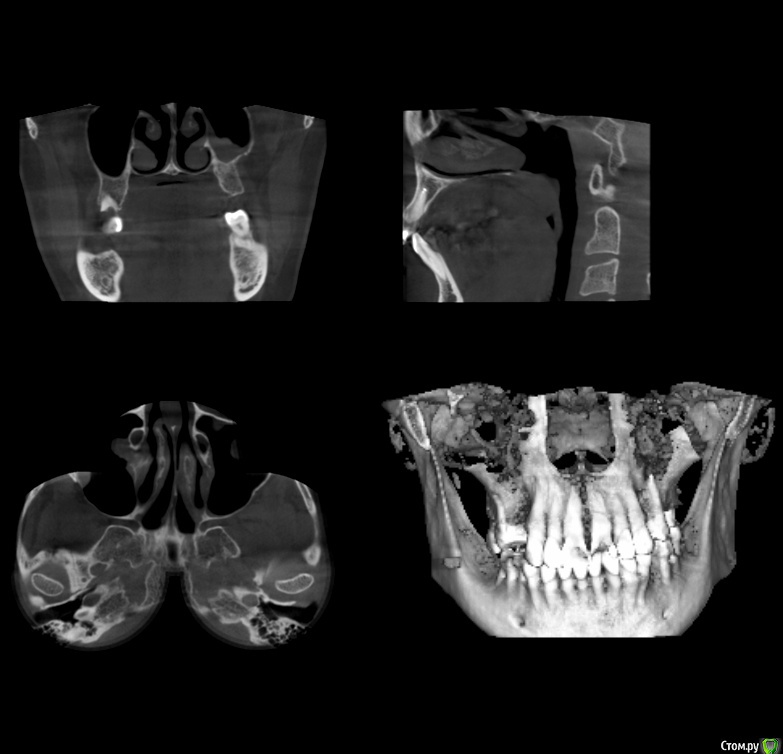

gum Опубликовано 15 сентября, 2015 Поделиться Опубликовано 15 сентября, 2015 Коллеги здравствуйте. У пациентки планируется двусторонний синус лифт, но по кт в пазухе проблемы. Клинически пациентка никогда не жаловалась. Отправил к ЛОРу было проведено терапевтическое лечение. ЛОР сказала, что не видит преград для операции. Соустьев на КТ не видно. Отправлять к другому ЛОРу? и вообще как при таких изменениях в пазухе проводить операцию. Подскажите какую литературу лучше почитать, Ссылка на комментарий

gum Опубликовано 28 сентября, 2015 Автор Поделиться Опубликовано 28 сентября, 2015 Пациентка принесла новый 3D. С пазухами. Слева сообщение с полостью носа есть, а справа по снимку оно не прослеживается.. Можно ли делать открытый синус лифт или к другому ЛОРу отправлять Ссылка на комментарий